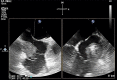

Introduction: Mural infective endocarditis (MIE) is a rare type of endovascular infection. We present a comprehensive series of patients with mural endocarditis.

Results: Twenty-seven MIEs out of 3676 IEs were included. When compared to valvular IE (VIE) or device-associated IE (DIE), patients with MIE were younger (median age 59 years, p < 0.01). Transplantation (18.5% versus 1.6% VIE and 2% DIE, p < 0.01), hemodialysis (18.5% versus 4.3% VIE and 4.4% DIE, p = 0.006), catheter source (59.3% versus 9.7% VIE and 8.8% DIE, p < 0.01) and Candida etiology (22.2% versus 2% DIE and 1.2% VIE, p < 0.01) were more common in MIE, whereas the Charlson Index was lower (4 versus 5 in non-MIE, p = 0.006). Mortality was similar. MIE from the literature shared many characteristics with MIE from GAMES, although patients were younger (45 years vs. 56 years, p < 0.001), the Charlson Index was lower (1.3 vs. 4.3, p = 0.0001), catheter source was less common (13.9% vs. 59.3%) and there were more IVDUs (25% vs. 3.7%). S. aureus was the most frequent microorganism (50%, p = 0.035). Systemic complications were more common but mortality was similar.

Conclusion: MIE is a rare entity. It is often a complication of catheter use, particularly in immunocompromised and hemodialysis patients. Fungal etiology is common. Mortality is similar to other IEs.